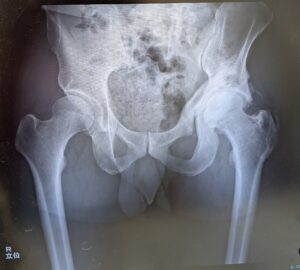

レントゲンは直ぐに呼ばれて、臥位と立位で合計3枚撮影。